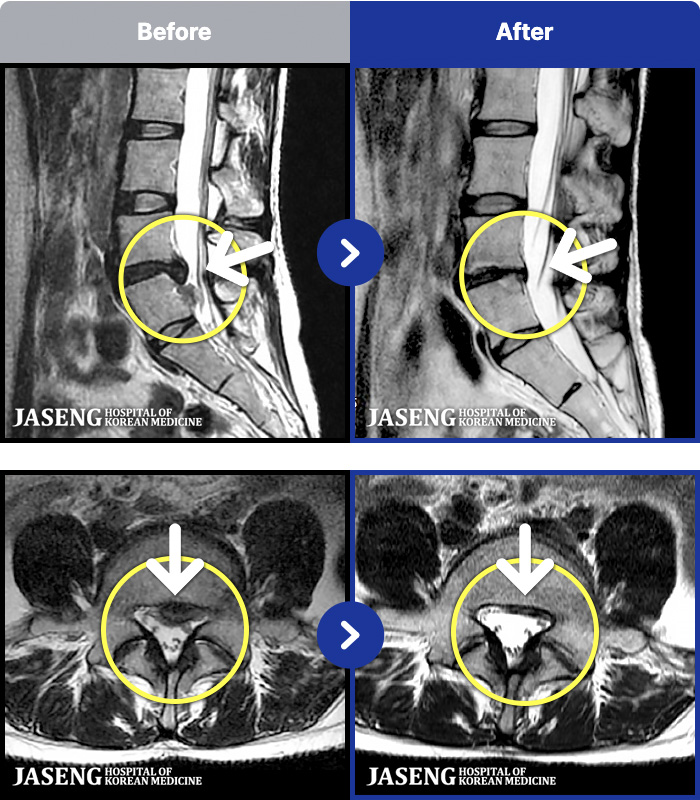

- MRI ġ

MRI ġ

191 MRI ũ ʸ Ȯϼ.

[_㸮ũ] ٸ 㸮 ȹٷ , Բ 㸮 ־ ߴ.